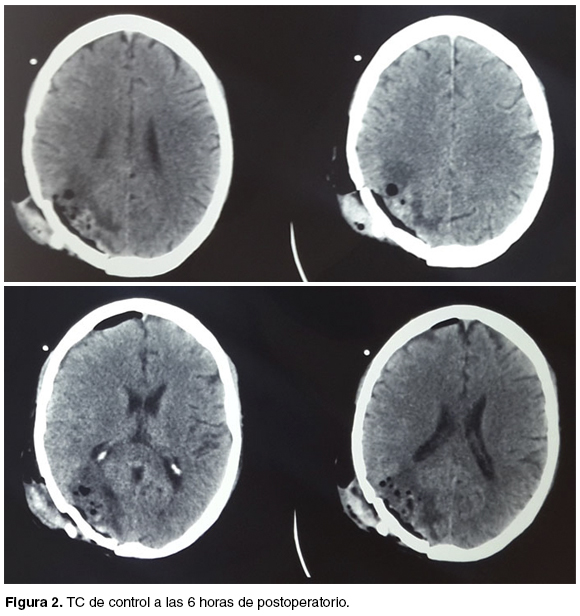

Egresa de block quirúrgico a la Unidad de Cuidados Intensivos (UCI) intubado, bajo sedoanalgesia. La tomografía (TC) de control a las 6 horas de postoperatorio, no muestra complicaciones hemorrágicas en el lecho (figura 2). El paciente lograba una apertura ocular al llamado y cumplía órdenes.